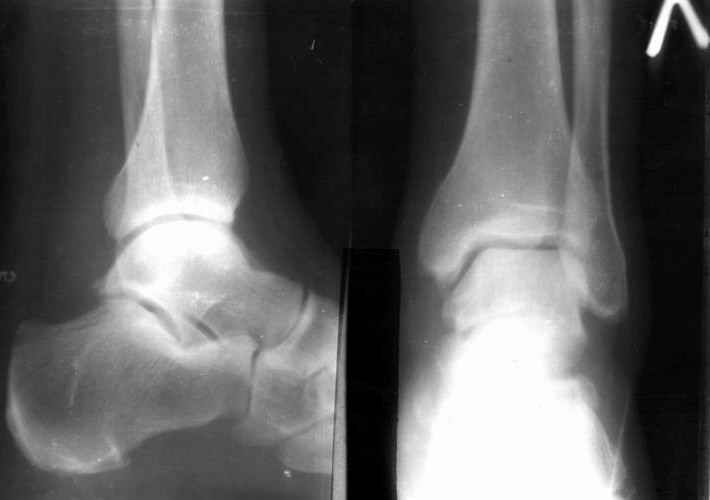

братился мужчина, 50 лет. Жалобы на боли в голеностопном суставе, периодическое подворачивание стопы вовнутрь. Получил травму 5 лет назад. При осмотре - признаки латеральной нестабильности, боли по ходу малоберцово-таранной, задней малоберцово-пяточной связки. Сделал стандартный Rg, и Rg с нагрузкой. В течение последнего года начали беспокоить боли в коленном, тазобедренном суставе. Как полагаю, это связано с нарушением биомеханики всей ноги. Если прооперировать и устранть нестабильность, пройдут ли эти боли (этот вопрос пациент задал сразу, как только услышал слово операция)? С ув. Сергей Мелашенко, Приморск, Запорожская обл. Ukraine

Попробуйте сделать аналогичный стресс -снимок прямой проекции здорового сустава и сравнив его с ранее травмированной стороной определитесь есть

нестабильность или нет.

присоединяюсь к мнению показать симметричные снимки

пока не кажется, что нестабильность очевидна.